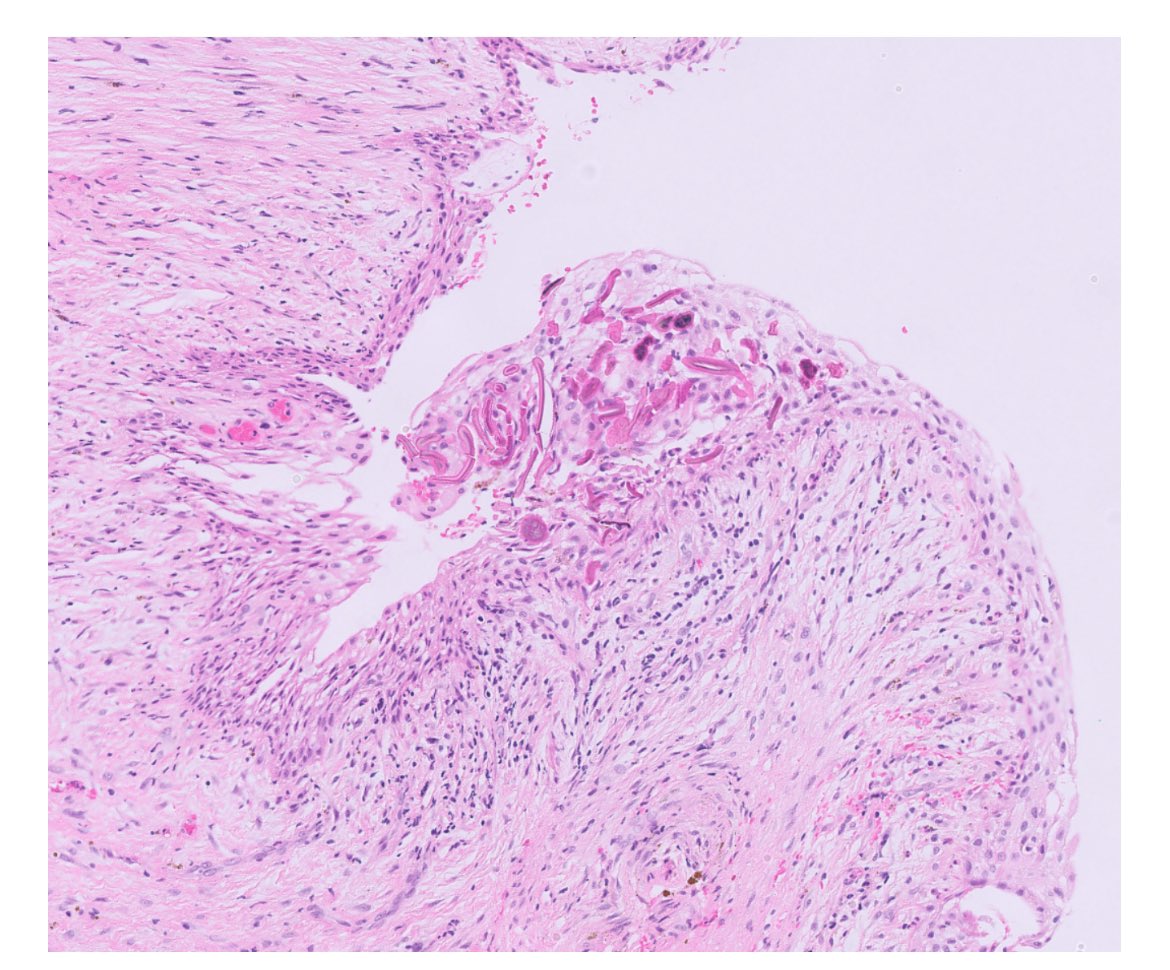

45 year old male with testicular mass, pleural and pericardial effusions. 5 cm tender testis. Systemic symptoms resolved after orchiectomy. #GUpath